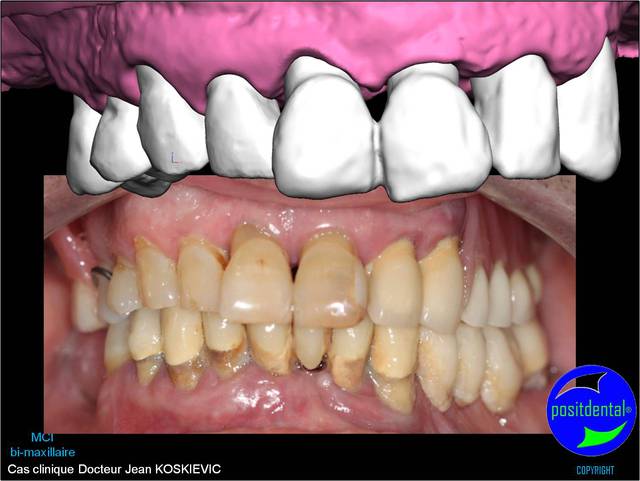

Montage esthétique ou wax-up 3D

Mci - Eugenol